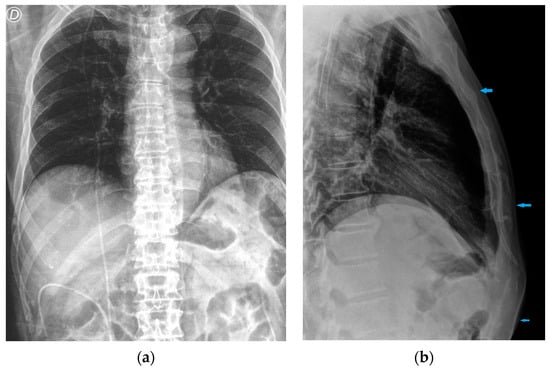

| Chest tubes | Kinking Extrapleural/intrafissural/intraparenchymal/misposition Mediastinum juxtaposition Diaphragmatic trespassing Mediastinal invasion (uncommon) |